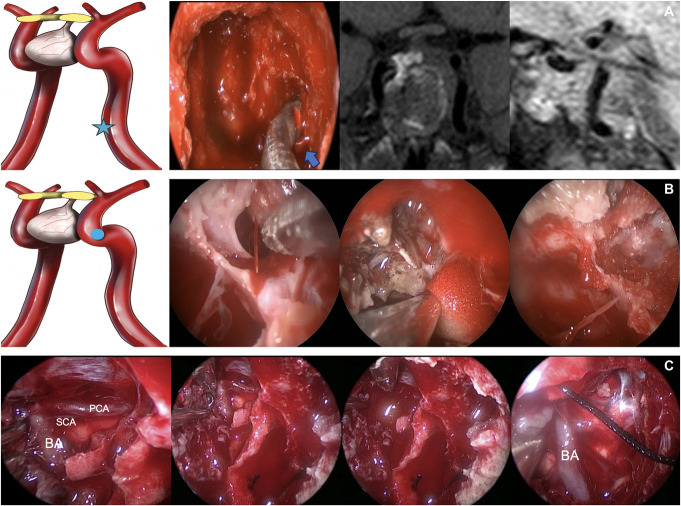

背景与目的:内窥镜鼻内手术(EES)因其全景性和详细的解剖定义而成为治疗鞍区和鞍旁病变的首选方法。本研究旨在回顾EES的主要动脉损伤,这是一种罕见但严重的并发症,具有高死亡率和发病率。方法:回顾性分析1997年8月至2024年2月在我中心/神经外科进行的5640例EES手术中的15例患者。该研究侧重于围手术期和术后管理策略,强调使用氧化再生纤维素(Surgicel®)/明胶凝血酶基质(Floseal®)和多学科合作来实现止血。结果:大动脉损伤发生率为0.2%,患者平均年龄38.4岁,男女比例为10:5。最常见的肿瘤是腺瘤(n = 7)和脊索瘤(n = 5)。6例患者中最常见的出血动脉分别是颈内动脉海绵状段和颈门旁动脉。10例患者出现低流量出血,5例患者出现高流量出血,其中4例复发(P < 0.05)。3例颈动脉段高流量出血患者行数字减影血管造影置入支架或线圈栓塞,1例高流量出血患者行数字减影血管造影监测脑血流。1例患者在随访第14个月时死于心肌梗死,1例患者出现左偏瘫。结论:该研究强调了术前计划、外科专业知识和多学科团队合作在EES中处理主要动脉损伤的重要性。作者主张发展标准化的治疗算法,以改善这些患者的预后。这些发现弥补了EES中处理颈内动脉损伤的有限文献,强调了持续研究和算法开发的必要性。

Results: The incidence of major arterial injury was 0.2%, with a mean patient age of 38.4 years and a female-to-male ratio of 10:5. The most common tumors were adenomas (n = 7) and chordomas (n = 5). The most commonly bleeding arteries in 6 patients each are the cavernous segment of the internal carotid artery and the paraclival carotid artery. Low-flow bleeding was observed in 10 of our patients, while high-flow bleeding was seen in 5 patients, 4 of whom were recurrent cases ( P < .05). In 3 patients with high-flow bleeding from segments of the carotid artery, digital subtraction angiography was performed for stent placement or coil embolization, while in 1 patient with high-flow bleeding, digital subtraction angiography was used for monitoring cerebral blood flow. One of our patients died of a myocardial infarction at the 14th month of follow-up and 1 of our patients developed left-hemiparesis.